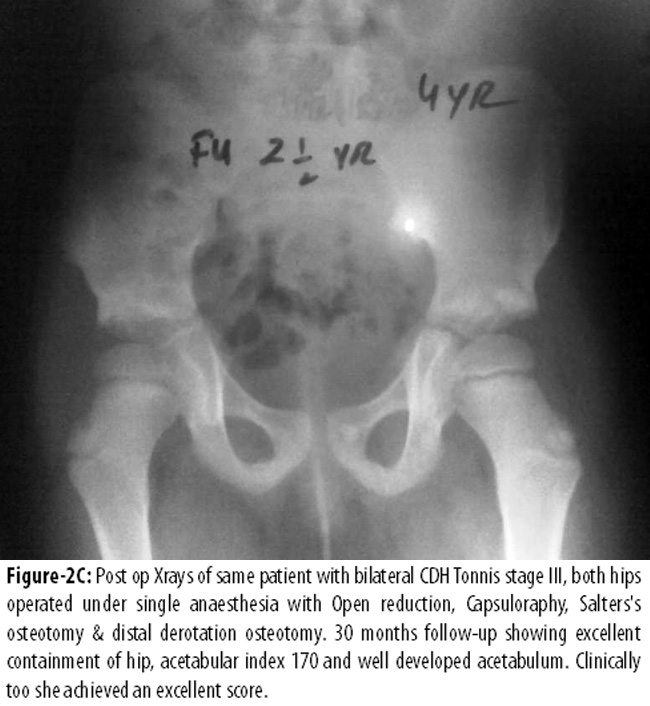

Figure-2AB shows Tonnis level III11 dislocated hips on both sides, with an acetabular index over 50° in an 18 months aged patient.

Figure-2C appreciates excellent contained hips, acetabular index 17° and a well developed hip at 30 months follow-up.